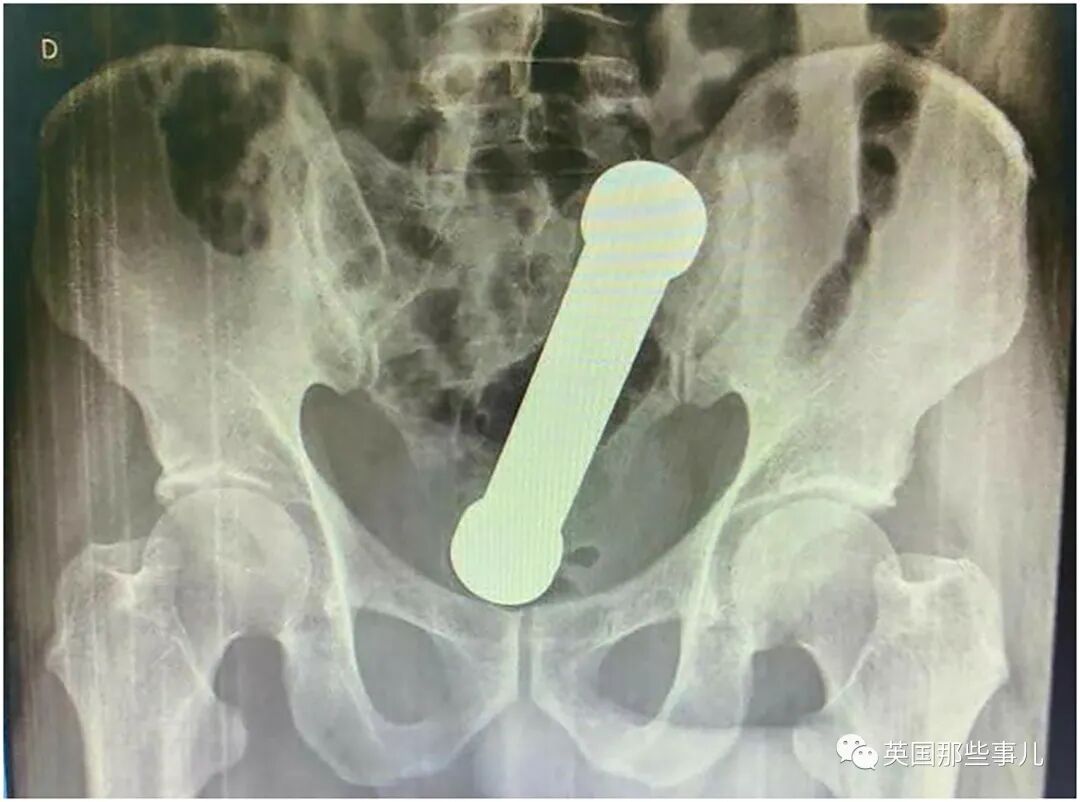

X光片显示,可以明显看到,

一个近20厘米长的哑铃,卡在结肠与直肠的交汇处。

这一发现,也印证了医生之前的猜测。